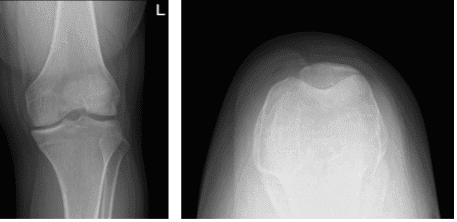

El paciente es un hombre de 19 años con dolor en la rodilla izquierda. Empezó después de que resbalara mientras jugaba al fútbol en casa. Se presentaron y revisaron sus radiografías, aunque no hay fracturas degenerativas significativas ni agudas.

Su historial y exploración sugieren fuertemente una rotura del LCA con posible rotura lateral del menisco de la rodilla izquierda. No había otros síntomas. En este momento se requieren pruebas diagnósticas adicionales. El paciente mueve la rodilla y hace WBAT con muletas.

Radiografía de rodilla izquierda con rótula